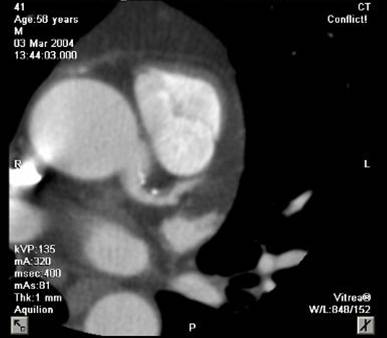

The non-invasive imaging modality of multi-detector computed tomography has dramatically evolved the last ten years and that is due to hardware and software developments. The newer generation of scanners allows increased spatial and temporal resolution that improves the clinical reliability giving further insights into the evaluation of coronary artery disease. Heart morphology imaging followed by studies of myocardial function and assessment of cardiac valves can be performed from the information derived from the data of the coronary artery examination. Also, the venous anatomy of the heart, coronary artery bypass grafts, stents, and cardiac tumors can be imaged and evaluated when necessary. For the beneficial use of this method, entrance criteria for different patient groups need to be set in order to allow improved outcome of multi-detector CT.